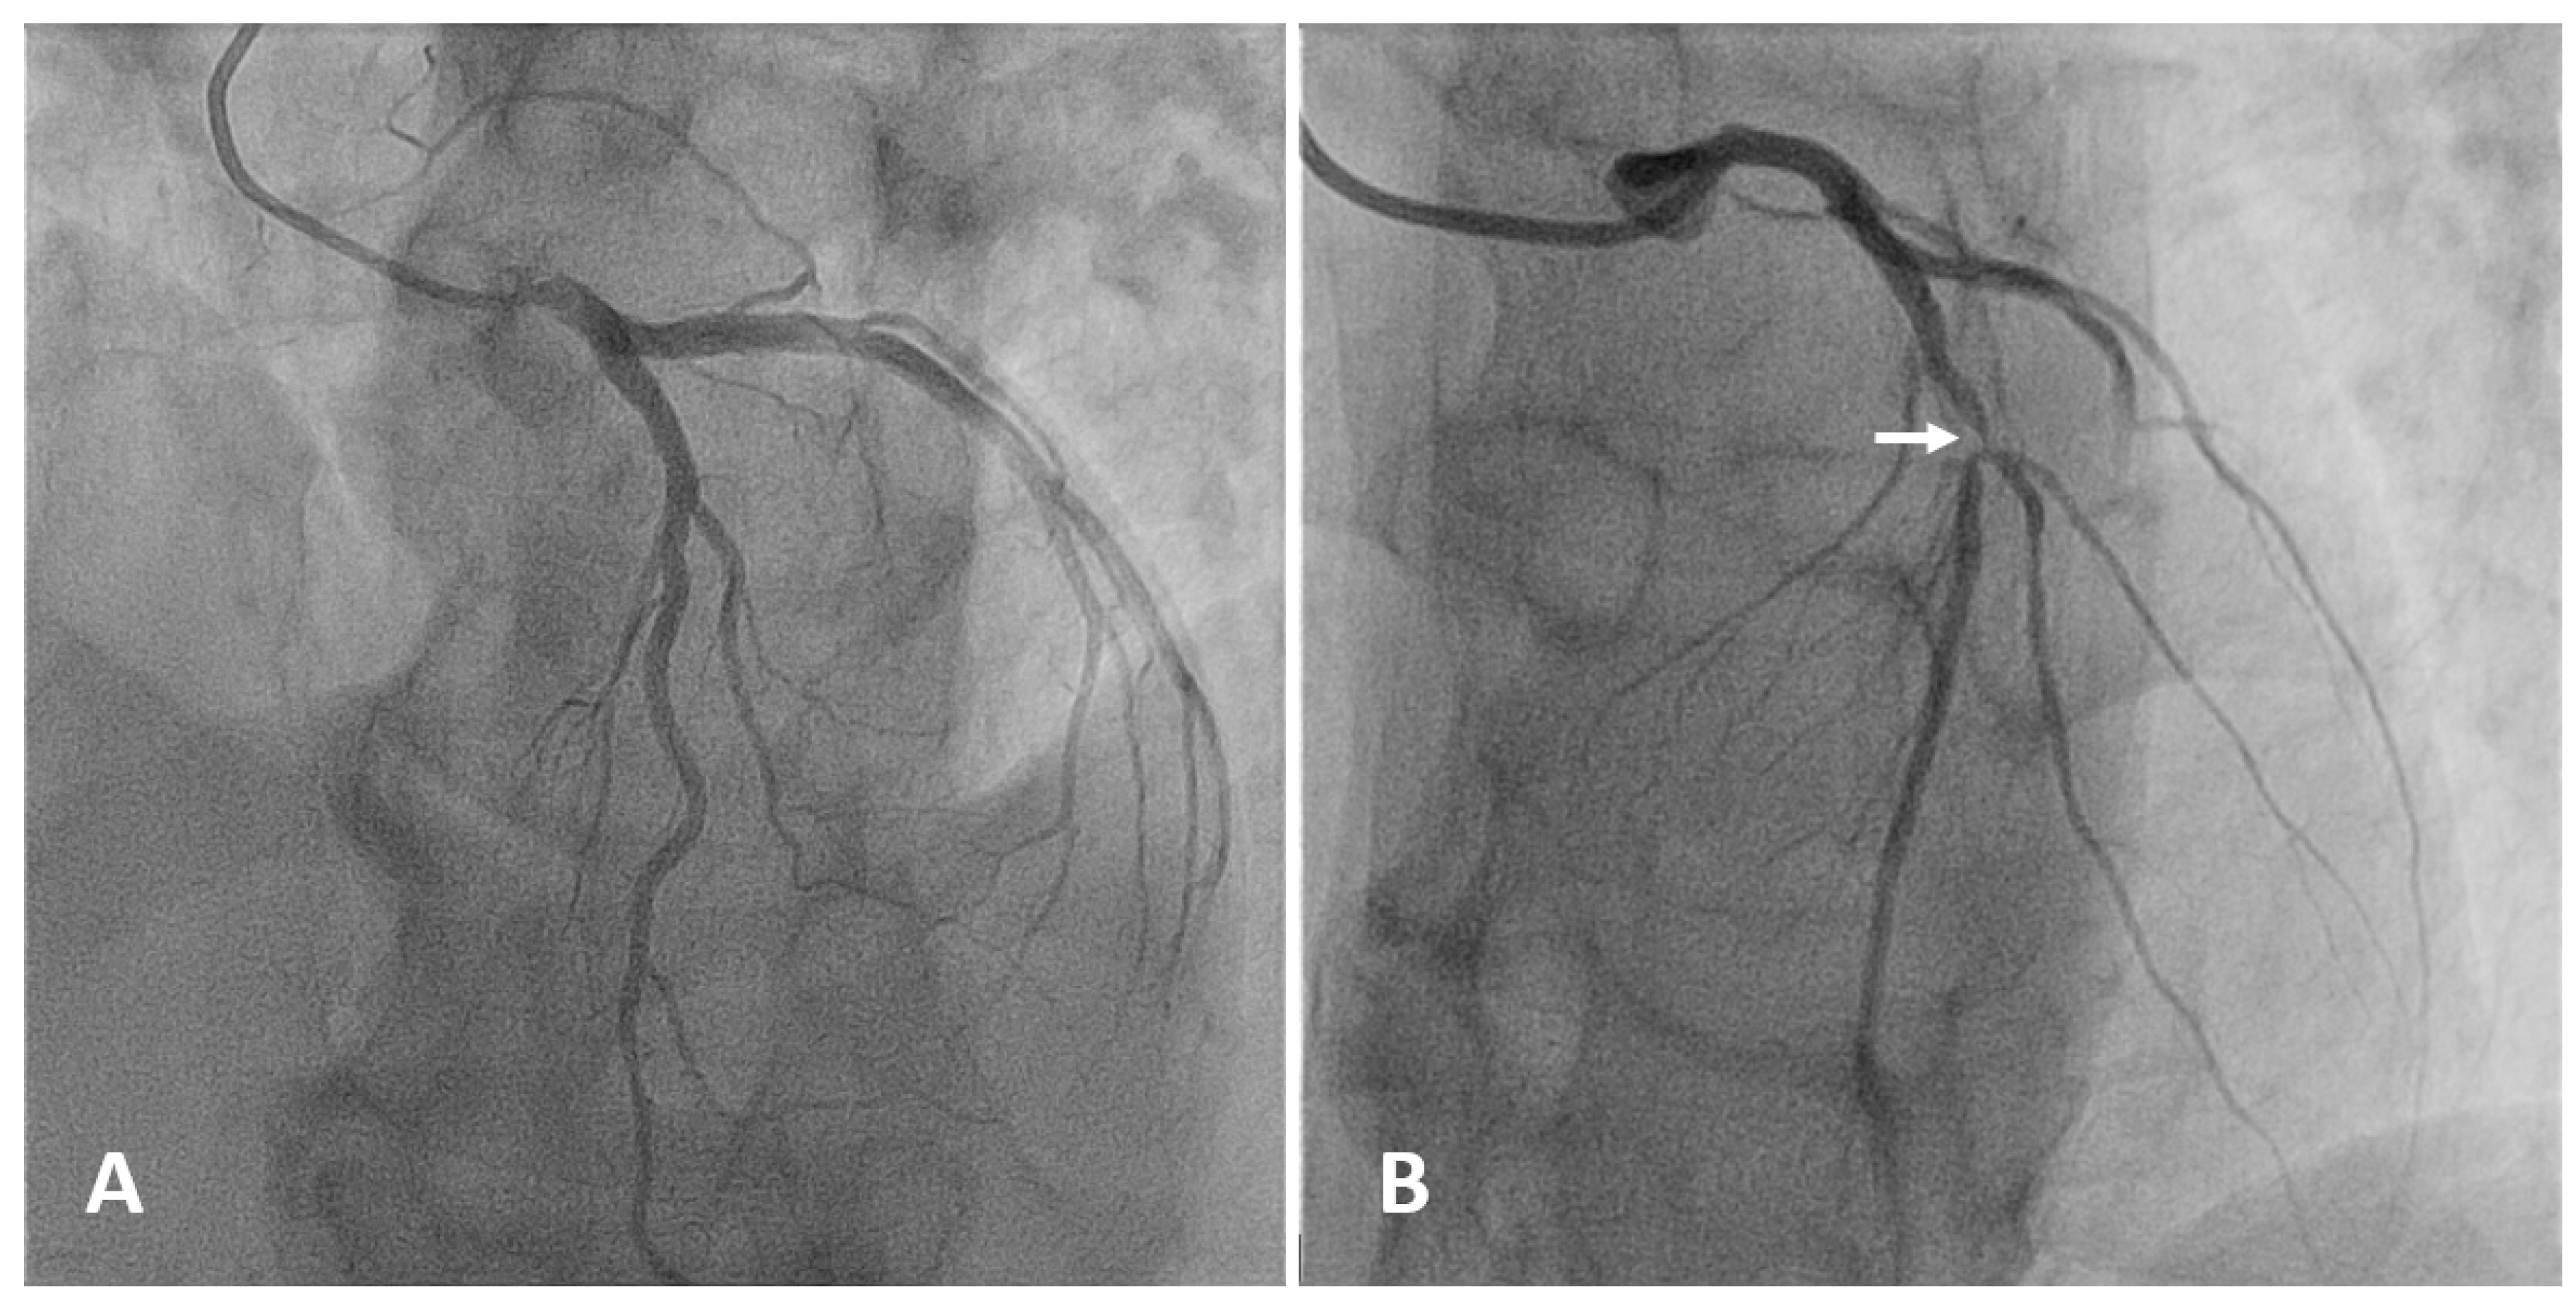

Coronary angiography is the anatomic reference standard for coronary imaging. Providing direct visualization of the degree of luminal narrowing with excellent spatial and temporal resolution, it is the imaging modality of choice for symptomatic, high-risk patients (Figure 4). Compared to intravascular ultrasound or optical coherence tomography, coronary angiography has low sensitivity. While large calcified plaques are well visualized, the sensitivity for smaller lesions is limited, due to low spatial resolution (about 1 mm) [100]. Although angiography is optimal for outlining contrast-filled coronary lumen, it cannot provide information on structures that are below the endothelium. The atherosclerotic burden, especially in the earlier stage of disease when positive coronary remodeling may allow apparently normal lumen size despite the presence of wall plaques, is underestimated. Also, the degree of anatomic stenosis is only modestly correlated with hemodynamic functional significance [101]. Since most acute coronary syndromes are not consequences of occlusion at the site of severe stenosis but result from rupture of small plaques associated with only mild to moderate stenosis, angiography is limited in predicting CV events [2,102].

Figure 4.

Selective angiography of the left coronary artery. (A) Normal coronary anatomy: left main, left anterior descending (LAD), left circumflex, and their branches are patent. (B) Focal severe narrowing of the lumen (arrow) due to a 90% stenosis in the proximal segment of the LAD.